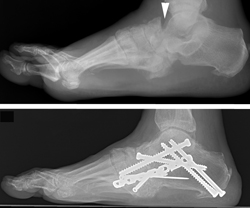

Radiografías. Las radiografías brindan imágenes detalladas de las estructuras densas, como los huesos. En la etapa muy temprana de Charcot, las imágenes proporcionadas por las radiografías pueden ser normales. Sin embargo, en casos más graves, pueden verse fracturas y fragmentos óseos en las radiografías. A medida que avanza la afección, las deformidades pueden volverse más drásticas, lo que puede derivar en luxaciones, destrucción de las articulaciones y formación de tejido óseo.

Exploración por tomografía computarizada (TC). Una TC es un tipo de radiografía tridimensional que puede proporcionar una imagen muy detallada de los huesos. Es probable que su médico le ordene una TC si considera que necesita una cirugía para el pie de Charcot. La TC detallada puede ser muy útil para planificar exactamente qué tipo de cirugía necesita.

- Corrección de deformidades en el pie de Charcot. Cuando las fracturas y luxaciones son inestables o los huesos están significativamente desalineados, puede ser necesaria la colocación de placas, tornillos o barras para corregir las deformidades y lograr que los huesos se consoliden en una posición adecuada. Debido a la calidad ósea deficiente, las fracturas que ocurren en los diabéticos suelen ser más complejas. Por lo tanto, las cirugías para corregirlas suelen requerir más implantes (placas y tornillos) que los que serían necesarios en pacientes no diabéticos. Si se realiza cualquiera de estas operaciones, también puede utilizarse un injerto de hueso para ayudar a que los huesos se consoliden.

- La artrodesis articular (fusión de articulación) es un tipo de cirugía en la que los huesos luxados se fijan en un fragmento de hueso sólido. Las fusiones de articulación son operaciones eficaces para corregir deformidades y mejorar la estabilidad; por ende, son una pilar en el tratamiento del pie de Charcot.

- Para las fracturas agudas sin luxaciones importantes, puede ser suficiente solo reparar los huesos fracturados (reducción abierta y fijación interna).

- Para las deformidades significativas, particularmente del talón o el tobillo, puede ser necesario insertar una barra grande en el tobillo para mantener la estabilidad.